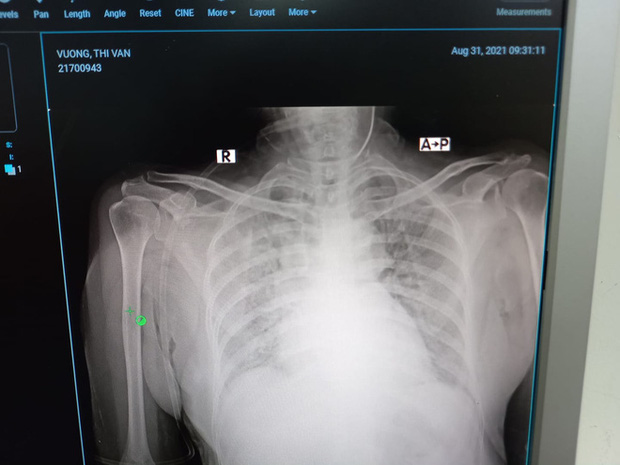

Ca bệnh đặc biệt này thật bất ngờ vì ngay khi nhận buồng mọi người đã bảo, ca này nặng đấy nhé, tràn khí trung thất, tràn khí dưới da. Tức là bệnh nhân này đã bị Covid-19 ăn thủng phổi, nếu trong mấy ngày tới có nặng lên thì cũng không thở máy được, vì đang tràn khí màng phổi. Như vậy khả năng tử vong gần như chắc chắn.

Nhưng thật lòng, bác sĩ Dân thấy anh khó qua khỏi. Xét nghiệm thì thấy các chỉ số của bão cytokine đang hoành hành dữ dội. Hai lá phổi viêm trắng xóa. Bác sĩ phải dùng tối đa oxy hỗ trợ: thở oxy dòng cao HFNC 60 lít/phút, rồi lại chụp thêm ra ngoài một cái mask oxy 15 lít/phút. Oxy phun ào ào như thác lũ nhưng phổi viêm nặng như thế, oxy cũng không vào máu.

BS Dân cho biết buổi chiều 3/9, bác sĩ đưa bệnh nhân chụp cắt lớp CT phổi. Nhìn phổi của bệnh nhân đông đặc gần hết chỉ còn một chút phổi lành, nhưng bệnh nhân đã cai oxy dòng cao được. BS Dân cho biết đây là điều thật kỳ diệu.